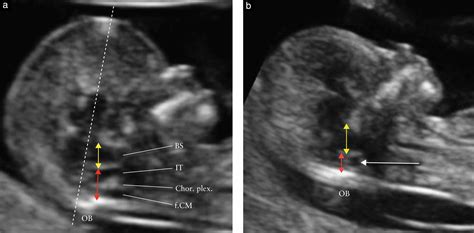

An Ultrasound 12 Workweek scan, also known as the nuchal semitransparency scan, is typically perform between 10 weeks and 13 week and 6 days of gestation. This non-invasive operation uses high-frequency sound waves to create images of the fetus. The primary end of this scan are to:

• Blind for chromosomal abnormalities, such as Down syndrome, by measure the nuchal semitransparency (the fluid-filled infinite at the back of the child's neck).

• Nuchal Translucency: The measuring of the nuchal translucency helps assess the risk of chromosomal abnormalities.

Interpreting the Nuchal Translucency Measurement

The nuchal translucency measure is a all-important component of the Ultrasound 12 Hebdomad scan. This measurement assesses the fluid-filled space at the back of the child's cervix. The thickness of this space can bespeak the risk of chromosomal abnormalcy, such as Down syndrome.

Here's how the nuchal translucency measurement is see:

• Low Jeopardy: A measurement within the normal range suggest a low danger of chromosomal abnormalcy.

• High Hazard: A measure above the normal range may betoken a high peril of chromosomal abnormalities. Farther quiz, such as amnio or NIPT, may be recommended.

It's crucial to understand that the nuchal translucence measurement is a screening test, not a symptomatic one. A high-risk resultant does not entail that the child unquestionably has a chromosomal abnormalcy, but it does guarantee further probe.